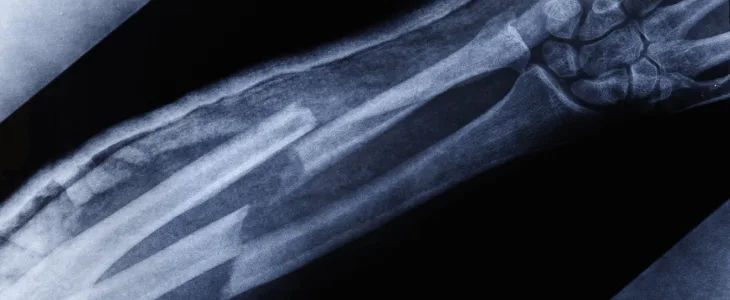

Car accidents can be life-altering events, often resulting in serious injuries such as broken bones— injuries that can have a significant physical, emotional, and financial impact on accident victims and their families. If you’ve suffered fractures due to someone else’s negligence on the road, you may be entitled to compensation. Here’s what you need to know to pursue your claim effectively and efficiently.

As a car accident victim in New York, you have the right to seek compensation for your injuries, including broken bones. New York follows a “no-fault” insurance system, which means that your own insurance company will cover some of your medical expenses and lost wages, regardless of who was at fault. However, broken bones entitle you to step outside the no-fault system and pursue additional compensation from the at-fault party.